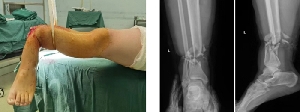

足踝外科成功完成1例小腿離斷再植術

近日,在手術室護理團隊、麻醉科團隊等科室的積極協(xié)助下,我院足踝外科歷時7個多小時成功完成1例“小腿離斷再植術”。當晚,值班醫(yī)師接到會診電話:患者趙某,男,29歲,因鋼板砸傷致左小腿離斷2小時急診入院。經初步評估,患者傷口遠端組織離斷,僅少許皮膚相連,遠端肢體無血運,創(chuàng)口內組織毀損嚴重。經與患者及其家屬充分